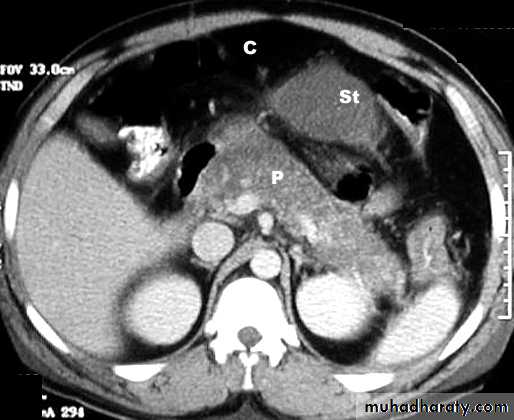

Radiology of acute pancreatitis

U/S

useful for biliary pathology, 70-80% sensitive for pancreatitisCT more useful for judging severity and regional effects